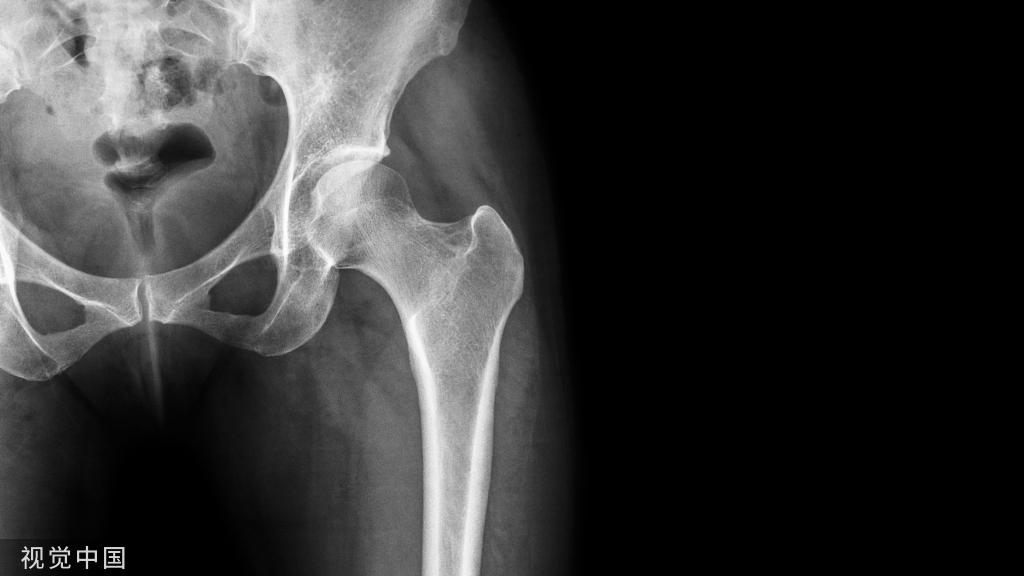

患者,男,60 岁,外伤后致右髋部肿痛,活动受限,无昏迷呕吐。

外伤后 X 线片显示:右股骨粗隆粉碎性骨折

体格检查:右髋部软组织肿胀明显,右股骨粗隆处压痛明显,患肢短缩、外旋畸形,活动受限。

临床诊断:右股骨粗隆粉碎性骨折。